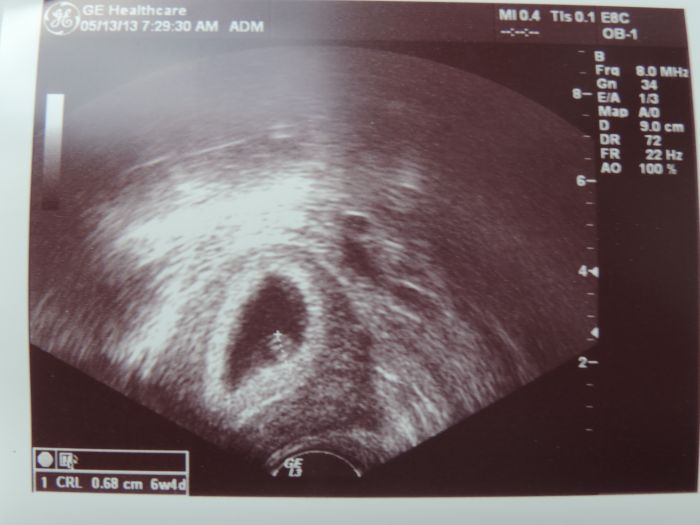

. No a po roce jsme se rozhodli, že to zkusíme ještě jednou.... a já zase otěhotněla !! Naštěstí dárkyně ještě nestimulovala, takže jsme to jen zrušili. Na ultrazvuku jsem byla v 6+2 a prcek 0,68cm se srdíčkem a velikostí 6+4 nás totálně odrovnal . Tak jsem stále v takovém stavu, kdy tomu ani nevěřím a nechci moc jásat, protože už vím jaké to je, jako asi hodně z Vás. Ale jak píše Barča, tentokrát mám takový lepší pocit... snad to tentokrát bude všechno v pořádku. Jestli můžu, zůstala bych tady u Vás.. ten termín bude +/- v prosinci :) Všem holčičky přeju pevné zdraví a ať už zvracíte, nebo ne... to přežijeme a těch našich uzlíčků se prostě dočkáme :)